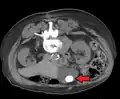

Large gallstone as seen on CT